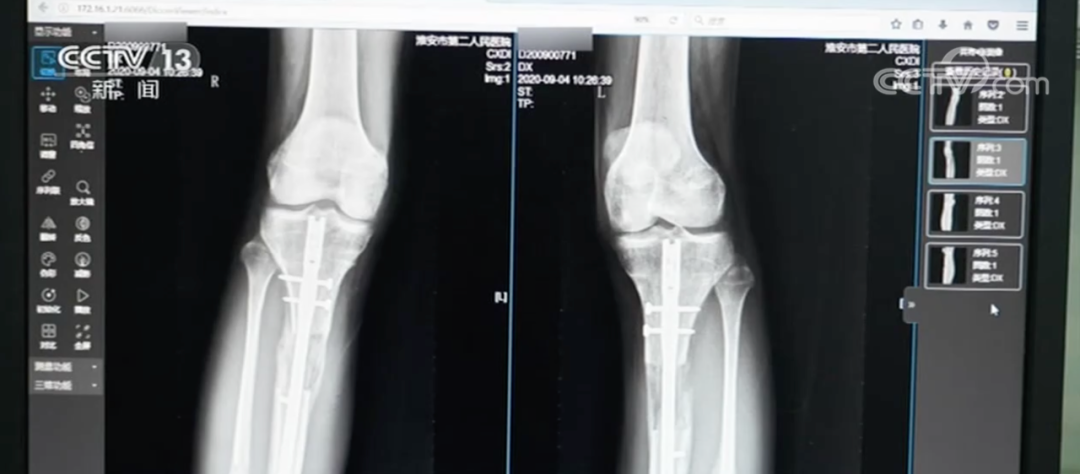

时至今日,小梦身体里的髓内钉依旧像一颗“定时炸弹”,无法取出。因为一旦贸然取出,极有可能引发二次骨折。更让她忧心忡忡的是,内置物中的磁铁成分说不定哪天就会生锈,内固定装置也随时面临断裂风险。虽说后来小梦在国内接受了 X 型腿矫正手术,可效果不尽人意。“我的腿脚老是酸疼,稍微多走一会儿路,就累得不行,又僵又硬,感觉腿上绑着沙袋似的,断骨的地方更是疼得钻心,连像正常人一样起身、蹲下都成了奢望。”小梦满脸苦涩地诉说着自己的痛苦。

60万“断骨增高”换来无尽痛苦,医美“禁区”亟待关注4.jpg